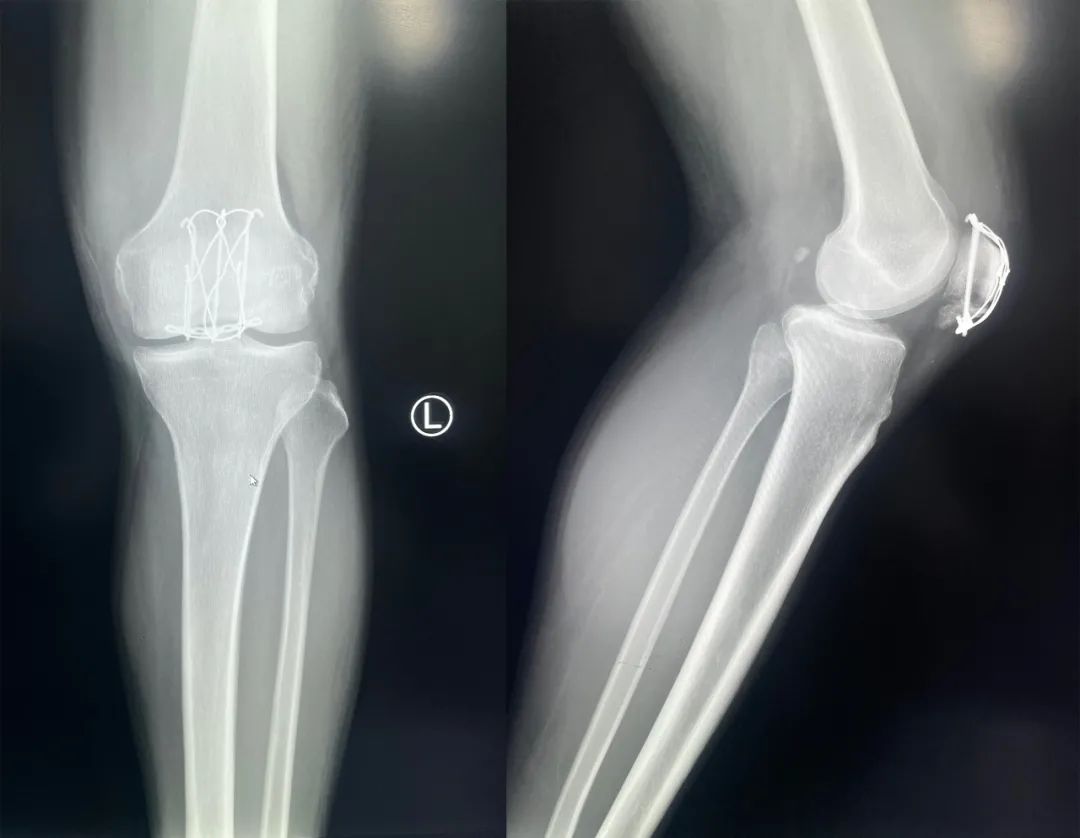

髌骨骨折只占全身骨折的 1%,治疗方式的选择和并发症的防治尤其要注意,急诊来了髌骨骨折患者,你怎么处理?髌骨是人体最大的籽骨,位于膝关节伸膝装置内。解剖特点包括近端宽大的基底和关节外的远侧尖端,前面位于关节外,后面为关节面。股直肌和股中间肌止于髌骨基底部,股内侧肌和股外侧肌止于髌骨的两侧。髌腱起于髌骨尖端,止于胫骨结节。髌骨骨折约占所有骨折的 1%,主要由直接暴力造成,如跌倒时跪地或膝关节屈曲时受到打击。典型的体征包括关节肿胀、压痛、伸膝功能部分或完全丧失。除以主诉和典型体征外,膝关节 X 线片也是必不可少的一项辅助检查,以膝关节正侧位 X 线片最常见,如果怀疑纵向骨折,膝关节屈曲 45° 时髌骨 30° 切位片可以辅助诊断。对于骨折不愈合、畸形愈合所致的关节面不平整以及髌股关节对应关系不良可采用 CT 检查。MRI 有助于诊断软骨缺损和损伤。34-B 型(部分关节内骨折,伸膝装置完整,如纵行骨折)髌骨下极骨折袢钢板结合克氏针、张力带固定 图源:作者提供

拉力螺钉加张力带钢丝固定或经胫骨结节绕髌环扎;经骨缝合撕裂的肌腱加髌骨和胫骨结节间钢丝环绕以加固缝合;袢钢板固定。无移位采用非手术治疗;移位并且单纯骨折采用横向拉力螺钉固定,骨质疏松患者需加环扎固定;对于多骨折块(星状)则采用髌骨环扎加张力带进行固定。克氏针加张力带钢丝;有第三个骨折块则采用拉力螺钉或克氏针加张力带钢丝固定;对于 4 个或 4 个以上的骨折块采用克氏针加螺钉加张力带钢丝进行固定;对于严重粉碎和软骨面广泛破坏的髌骨骨折,髌骨部分或完全切除也是一种可行的办法。

术中切开显露髌骨时,最理想的的分离层面为皮下筋膜和伸膝装置之间,如若在皮肤和皮下筋膜之间进行分离,可能会造成伤口边缘坏死。对于开放性髌骨骨折应及时给予清创处理,对于闭合性髌骨术后感染患者应及时进行清创灌洗直至伤口愈合。如有深部感染则推荐长期使用抗生素。透明降解物会产生轻重不等的无菌性滑膜炎,这很难和感染相区分。需行关节镜检查来确定。在进行克氏针固定髌骨时,克氏针的末端应剪短,否则有穿破皮肤以及术后活动时疼痛的风险。髌骨骨折术后内植物至少在损伤后 9 ~ 12 个月才能取出。高密度的骨皮质需要这么长时间才能愈合,从而能在无保护情况下承受高张力。必须防止这一并发症的发生,因为会导致膝关节屈曲严重受限。用环扎钢丝来保护髌腱时,有可能因为错误估计髌腱长度而造成髌骨低位。髌骨的正常位置可以参照健侧膝关节的 X 线片。屈曲受限的患者需要进行强化理疗。如果在数月内运动的范围没有增加,下一步可行关节镜下松解,去除髌上囊的挛缩瘢痕。如果髌骨已切除,则可能出现肌腱断裂的晚期并发症。髌骨软骨面的严重损伤、关节面不平整的继发性损伤以及髌股关节受力的改变,都将导致创伤性关节炎的发生。如果髌骨韧带附着位置太靠前方,会使髌骨下极位置靠后,也将导致创伤性关节炎。在前一种情况下,可以行关节镜下清理;后一种情况下需改变韧带附着点位置。髌骨术后应及时有效地进行膝关节活动锻炼,一般在术后 3 月时膝关节可屈曲 120° 以上,若术后 3 月时膝关节弯曲角度仍然小于 90°,建议进行辅助康复训练,必要时以手术松解。